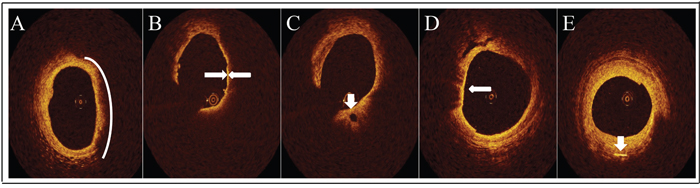

Only LRPs was analyzed in this trial. On the OCT image, LRPs was semi-quantified according to the maximal lipid arc. Lipid arc was measured at every 1 mm interval throughout the entire length of each lesion and the values were averaged. All the OCT images were analyzed using the previously validated criteria for plaque characterization. LRPs was defined as the plaque with lipid content > 100º and FCT< 120 μm on OCT image. FCT covering lipid core was measured at its thinnest part 3 times and the average value of the three measurements was used for subsequent analysis. At follow up, FCT was measured at the same site according to the landmark as it was measured at baseline using the same methodology. Lipid length was also measured on longitudinal view. Lipid index (LI) was defined as the averaged lipid arc multiplied by lipid length. The characteristic of lipid core was a diffusely bordered, signal-poor region (Figure 4A). TCFA was defined as a lipid-rich plaque with FCT ≤ 65μm (Figure 4B). Microchannel was defined as a black hole within a plaque with a diameter of 50-300μm and can be observed on at least 3 consecutive frames (Figure 4C). The characteristic of macrophages accumulation was a region with signal-rich, distinct or confluent punctuate heterogeneous backward shadows (Figure 4D).Cholesterol crystals were defined as linear and highly backscattering structures within the lipid-rich plaques (Figure 4E).

Figure 4: Representative OCT images. A. Lipid core (white arc) was defined as a diffusely bordered, signal-poor region. B. TCFA (white arrow) was defined as a lipid-rich plaque with fibrous cap thickness≤65μm. C. Micro-channel (white arrow) was defined as a black hole within a plaque with a diameter of 50-300μm and can be observed on at least 3 consecutive frames. D. Macrophages accumulation (white arrow) was a region with signal-rich, distinct or confluent punctuate heterogeneous backward shadows. E. Cholesterol crystal (white arrow) was defined as linear and highly backscattering structures within the lipid-rich plaques.